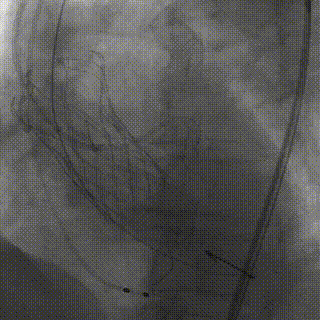

术中操作

冠脉处理前

冠脉处理后

球囊预扩

瓣膜释放

释放完成